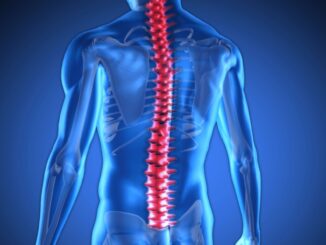

Lidské tělo je fascinující, složitý a dokonale fungující celek, ve kterém má každý orgán svou přesně danou roli. Každý den v našem organismu probíhají tisíce procesů, o nichž většinou ani netušíme, že se dějí. Srdce pumpuje krev, plíce zpracovávají kyslík, mozek vysílá signály, které se pohybují rychlostí blesku. Přestože své tělo používáme neustále, často nás překvapí, jak málo o něm víme. Víte například, který orgán je skutečně největší? Nebo kolikrát se průměrný člověk nadechne během jediného dne?

Lidské tělo je dokonalý stroj